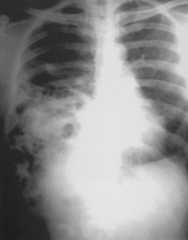

A thirty five year old male presented with breathlessness on routine exertion and symptoms of dyspepsia of a year duration. General physical examination was unremarkable, auscultation of the chest revealed presence of bowel sounds in the right side of the chest. Chest radiograph revealed a raised right hemidiaphragm, with its outlines not well discernible, mediastinal shift to the left and presence of air filled bowel loops in the right thoracic cavity (Fig 1). A provisional diagnosis of right sided diaphragmatic hernia was made and an upper gastrointestinal barium study was done which revealed presence of stomach, small intestine and parts of colon in the right thoracic cavity (Fig 2). A contrast enhanced CT scan of the thorax and abdomen was performed which confirmed presence of stomach, small intestine, large intestine and the right lobe of liver in the postero-lateral aspect of the thoracic cavity, discontinuity of the soft tissue line of the diaphragm with continuity of sub-diaphragmatic and supra-diaphragmatic densities through the defect suggestive of Bochdalek hernia (Fig 3). The right lobe of the liver was also hypoplastic. The patient was taken up for surgery and per operative findings revealed herniation of the stomach, coils of jejunum, ileum and colon through a smooth circular defect of 6cmx4cm size in the posterolateral aspect of the right hemidiphragm. The right lobe of the liver was hypoplastic and had herniated into the thoracic cavity. No hernial sac could be identified. The diaphragmatic defect was closed with polypropylene mesh and sutured in two layers with interrupted non-absorbable suture and the thoracic cavity was drained by a single chest tube. The patient had an uneventful postoperative recovery. A repeat upper GI barium study after 10 days of surgery revealed no evidence of any herniated bowel loop in the thoracic cavity (Fig 4).

Fig. 4.

Post operative upper GI barium studies showing no evidence of bowel loops in the thoracic cavity